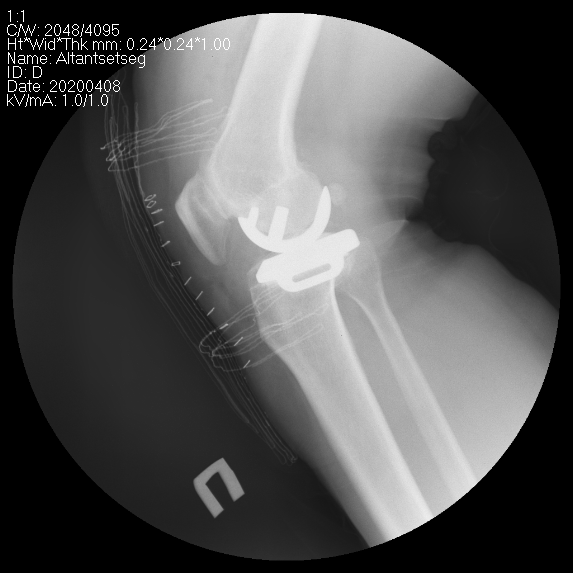

Өвдөгний үе хагас солих мэс засал (UKA) image2

Өвдөгний үеийг хэсэгчлэн солих мэс засалын төрөлд

• Дотор болон гадна булууг солих

• Тойгны үеийг солих

• Нэг талын булууг тойгны үетэй хамт солих мэс заслууд багтана.